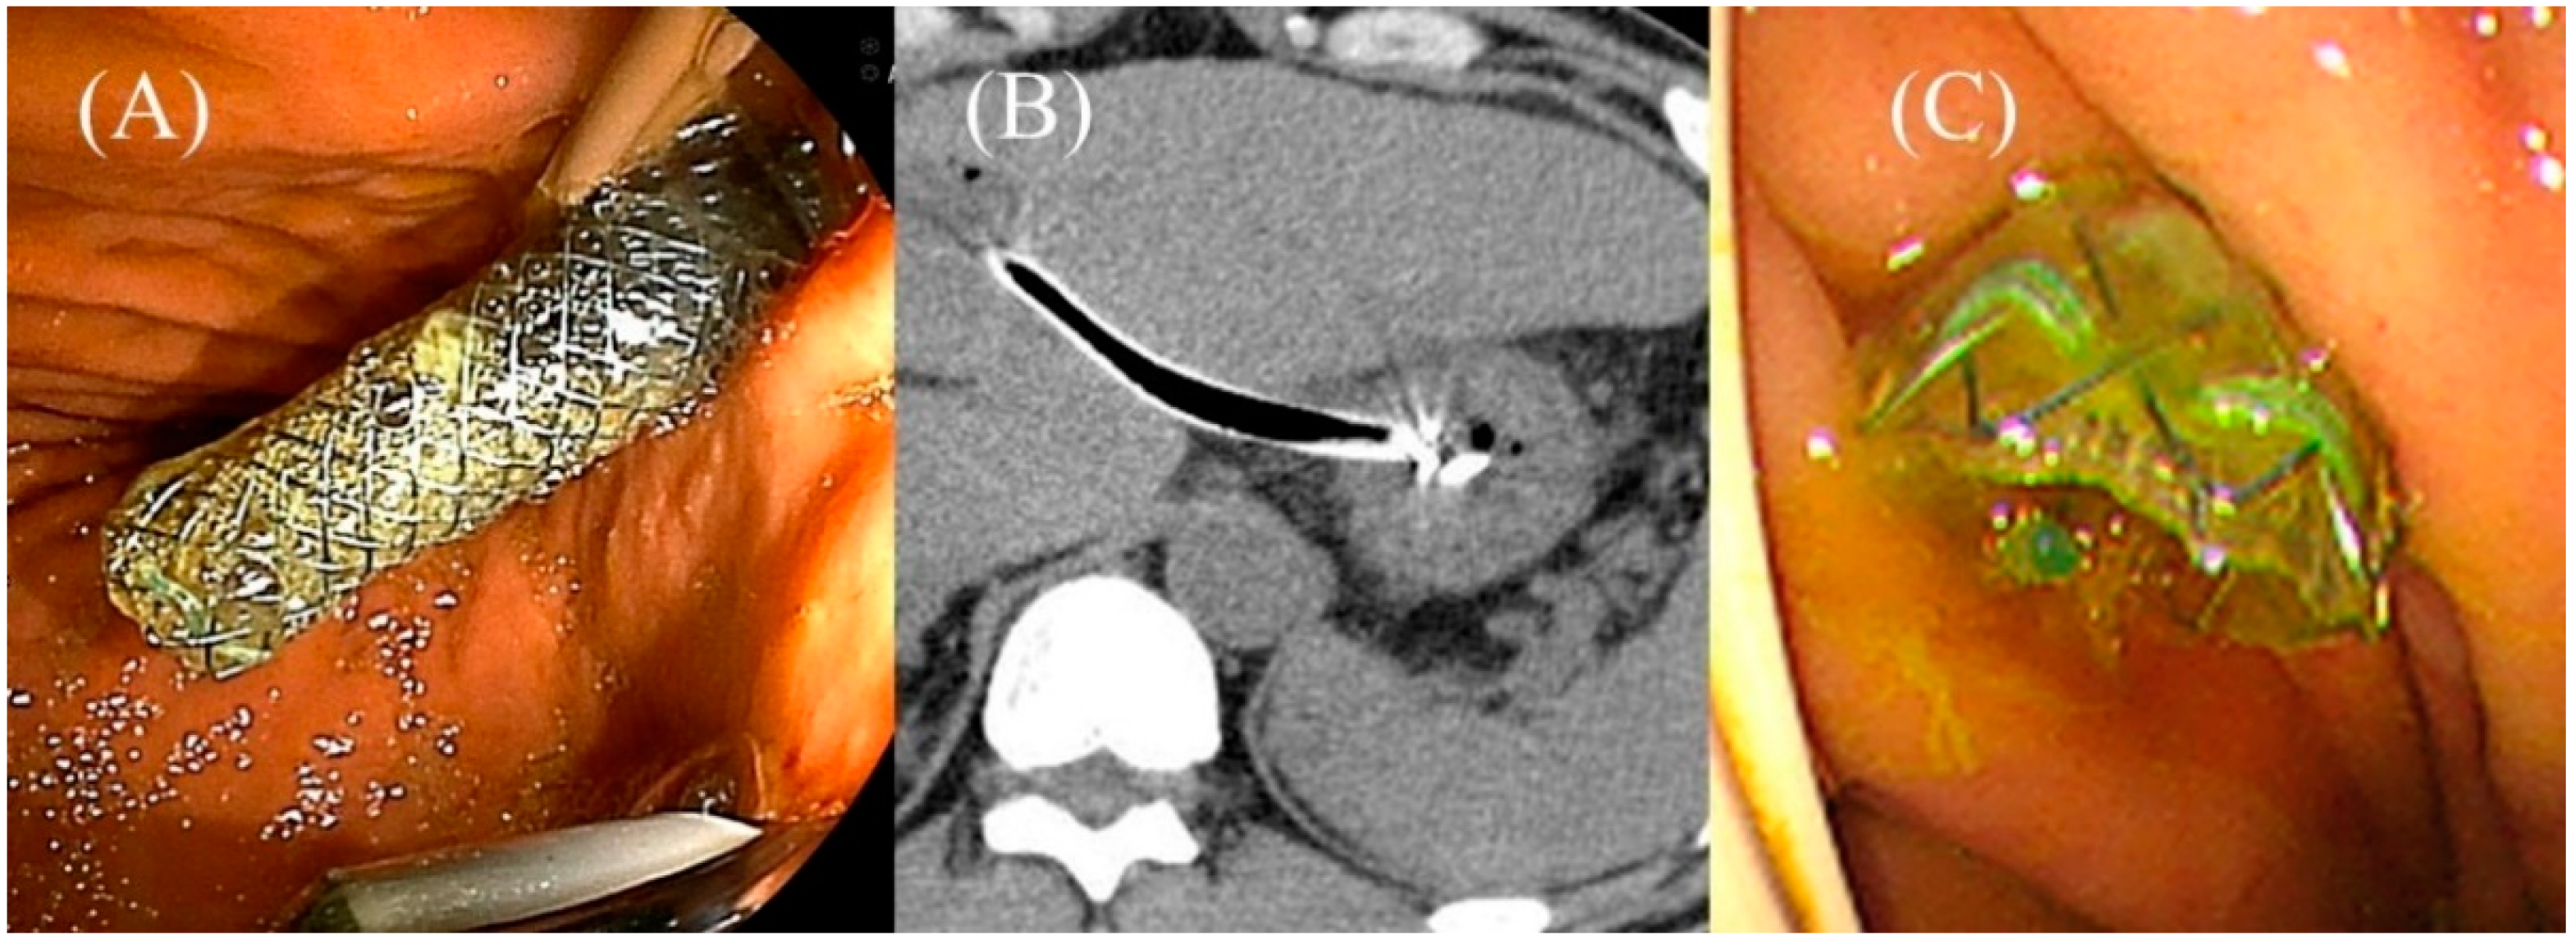

Figure 17.

Impending delayed migration in Niti-S S-type stent (Taewoong Medical). A sufficient length of the gastric end of the stent is seen after the procedure (A). The next day’s CT shows that the intragastric stent length has shortened (B). Urgent endoscopy reveals impending migration of the gastric end of the stent (C).

Migration can occur in two situations: early migration, when the stent detaches from the scope [63,64,65,66], and delayed migration, after successful deployment [16,62,67,68,69,70]. In EUS-HGS, the stomach and liver are initially brought in closer together by pushing the echoendoscope against the gastric wall. However, the distance between the liver and stomach becomes increased because the scope must be moved away from the gastric wall to eventually release the stent. This event and the shortening of the SEMS can cause early migration, in which the gastric end of the SEMS is pulled into the abdominal cavity. Recently, early migration can be avoided by using the “Intra-channel (conduit) release method” (see below), which can ensure that the end of the SEMS is placed in the stomach while minimizing the distance between the liver and stomach. However, since the stomach will eventually return to its original position, delayed migration may occur if the initial distance between the liver and stomach is long [21]. To prevent delayed migration, a long (≥10 cm) SEMS is recommended to ensure sufficient intragastric stent length [8,71,72]. Nakai et al. [71] and Ogura et al. [72] reported that sufficient intragastric length (>30–35 mm on CT the next day) may not only prevent delayed migration but also prolong stent patency by reducing the reflux of gastric juice and food. Nevertheless, even in cases with long intragastric stent length, the stent may be migrated by sudden gastric movements such as hiccups or vomiting [71]. Therefore, long stents with anti-migration properties may be optimal [21].

If abnormal findings are found on laboratory tests or physical examination the day after the procedure, or if sufficient intragastric stent length is not obtained during the procedure, a CT should be performed to check for possible abnormalities such as stent migration, pneumoperitoneum, or fluid collection. If the intragastric stent length is no longer sufficient due to stent shortening or gastric movement (impending migration; Figure 14B,C), there is a risk of migration of the gastric end of the stent into the abdominal cavity. In such cases, immediate endoscopic reintervention using various technique such as Crisscross anchoring technique [88], Clip-flap technique [89], and Stent-in-stent technique [90] should be performed to prevent stent migration. Pneumoperitoneum or fluid collection with new-onset abdominal pain or fever suggests bile leak, and antibiotics should be continued. If melena or an unexpected drop in hemoglobin is seen, a contrast-enhanced CT is necessary. When bleeding from hepatic artery is suspected, angiography should be performed urgently. The results of the pooled analysis of early adverse events of EUS-HGS described in the Japanese clinical practice guidelines are summarized in Table 2.